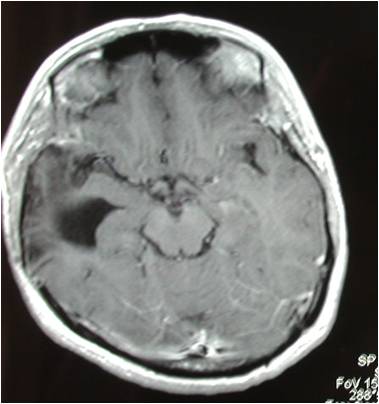

巨大中颅底脑膜瘤切除术

术前MRI提示肿瘤巨大,周围骨质破坏